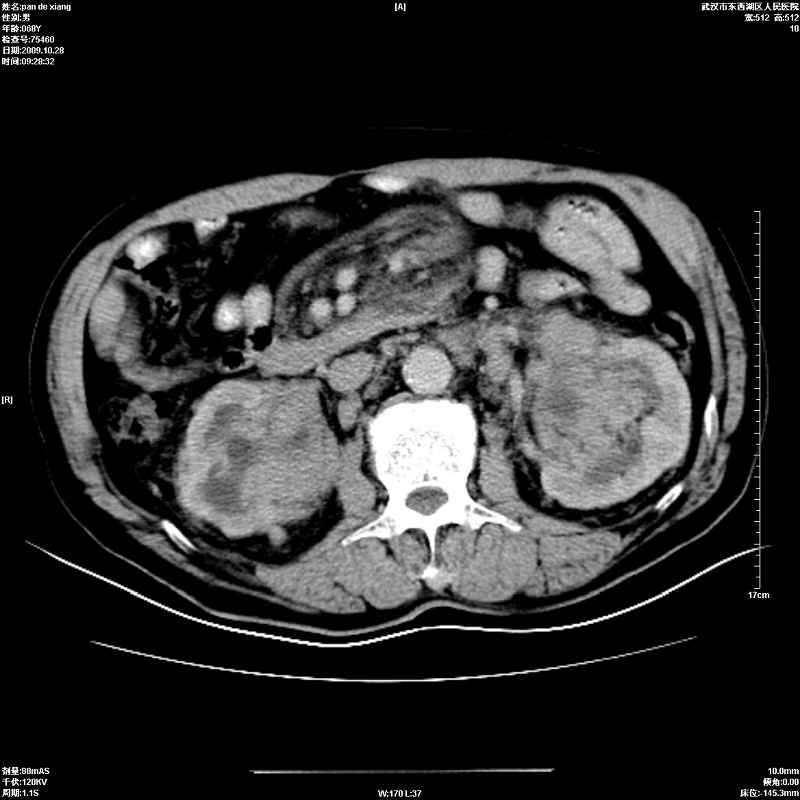

以下是引用杀毒软件在2009-10-28 20:41:00的发言:[br]结合临床考虑---白血病双肾改变或淋巴瘤。

以下是引用zxl51642在2009-10-29 9:59:00的发言:[br]结合临床“单克隆免疫球蛋白血症”,考虑双肾为继发损害并肾功能不全(尿中大量igg及少量iga、igm等大分子免疫球蛋白滤出所致继发损害),椎前软组织肿块为髓外造血。与浆细胞瘤有区别,平扫时有战友说的很清楚。